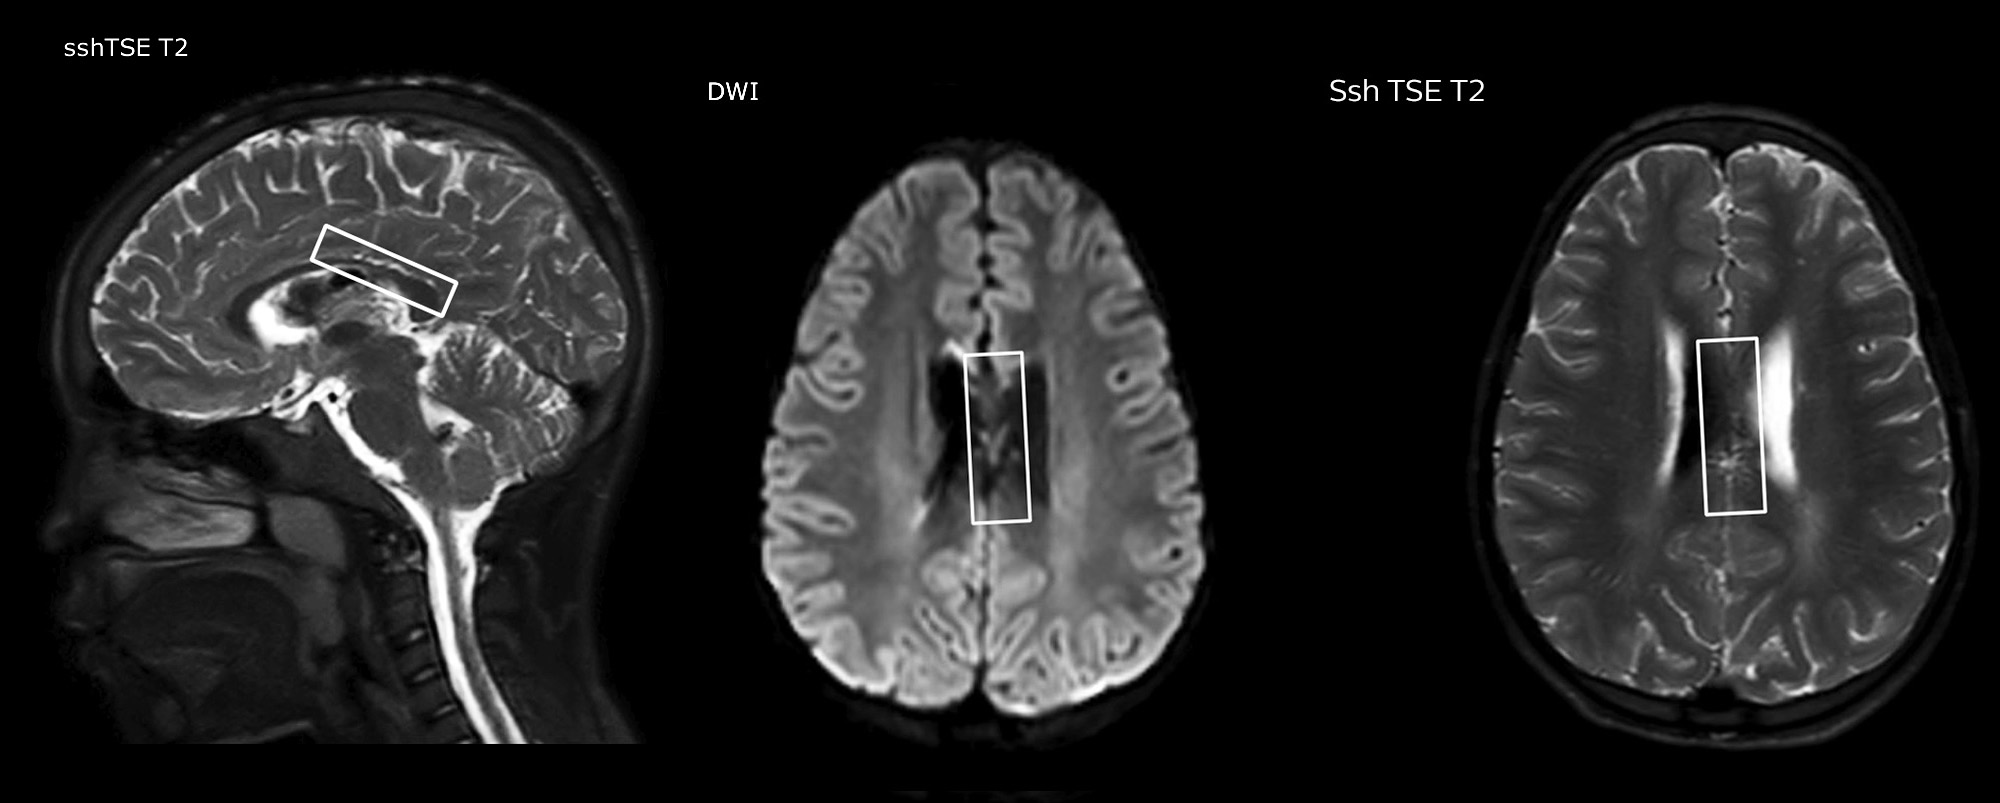

Pseudo-continuous arterial spin labeling (pCASL) was developed for brain perfusion imaging without contrast agent. “This is very desirable in pediatric patients where the general trend is to limit the administration of contrast,” says Dr. Miller.

Dr. Miller uses pCASL for all patients who present with chronic and acute cerebrovascular abnormalities such as acute stroke, as well as patients who present with signs of acute inflammation in the brain, and occasionally in patients with tumors, to assess the perfusion status of their tumor.

“In combination with diffusion weighted imaging, it can help give a more extended assessment of the degree of perfusion abnormality in a patient who is suffering acute ischemia. We have a number of patients who have chronic arterial insufficiency due to prior arterial abnormalities or acquired arterial abnormalities such as sickle cell disease or neurofibromatosis. Sometimes the child’s first manifestation of disease progression is a reduction in brain perfusion before stroke symptoms manifest clinically or in diffusion weighted imaging. We use pCASL to help delineate the perfusion abnormality.”

Growing confidence in specific applications

“We built up confidence in pCASL by comparing it to contrast-based perfusion imaging. Once we had confidence that it was representing what the contrast perfusions were representing, we increased our diagnostic confidence by serial imaging in either the acute stage or the long term stages in a number of patients with arterial abnormalities.

To other new users I would recommend to also start to interpret the pCASL images in comparison with other standard imaging – T2 and FLAIR and DWI – until the user gains confidence in interpreting these images by themselves.”

“A powerful use of pCASL is in patients with chronic cerebrovascular stenosis, where clinicians desire information on how compensatory mechanisms of the brain are performing to enable perfusion to the brain. Often clinicians take into account how the compensatory mechanisms appear to help to provide adequate perfusion to the patient’s brain, and they may intervene surgically or make some other management decision.”